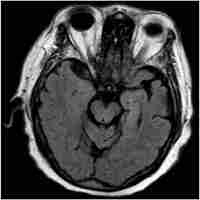

| Abstract | Agrammatic variant primary progressive aphasia is a neurodegenerative disorder specifically characterized by language deficits. A recent study has demonstrated a beneficial effect of transcranial direct current stimulation (tDCS) in combination with language training on naming accuracy in these patients. The aim of the study was to evaluate whether the improvement of naming accuracy after tDCS during language training was related to regional grey matter (GM) density. Eighteen avPPA patients underwent a brain magnetic resonance imaging before receiving a treatment that consisted of tDCS over the left dorsolateral prefrontal cortex during individualized language training (10 daily therapy sessions, 5 days per week from Monday to Friday). Performances on neuropsychological tests and naming of objects (treated and untreated) and actions were assessed at baseline, post-treatment and 3 months after treatment. Correlations between individual changes after treatment on neuropsychological tests and on picture naming task and voxel-based GM volume at baseline were performed. We found that the improvement in the naming of treated objects was positively correlated with GM volume in the left fusiform, left middle temporal, and right inferior temporal gyri whereas action naming change was related to GM density in the left middle temporal gyrus. In conclusion baseline density of GM in these brain regions was associated with greater treatment response on naming performances, suggesting that intervention in early disease stages might be most successful. These findings have implication for designing future rehabilitation protocols in language variants of frontotemporal dementia. |